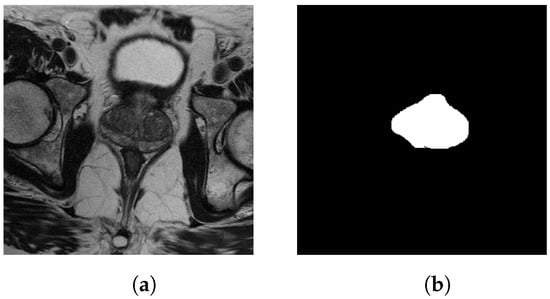

- Cairone, L.; Benfante, V.; Bignardi, S.; Marinozzi, F.; Yezzi, A.; Tuttolomondo, A.; Salvaggio, G.; Bini, F.; Comelli, A. Robustness of Radiomics Features to Varying Segmentation Algorithms in Magnetic Resonance Images. In Proceedings of the Image Analysis and Processing, ICIAP 2022 Workshops, ICIAP 2022; Lecture Notes in Computer Science; Frontoni, P.L.M., Sclaroff, S., Distante, C., Eds.; Springer: Berlin/Heidelberg, Germany, 2022; Volume 13373, pp. 462–472. [Google Scholar] [CrossRef]